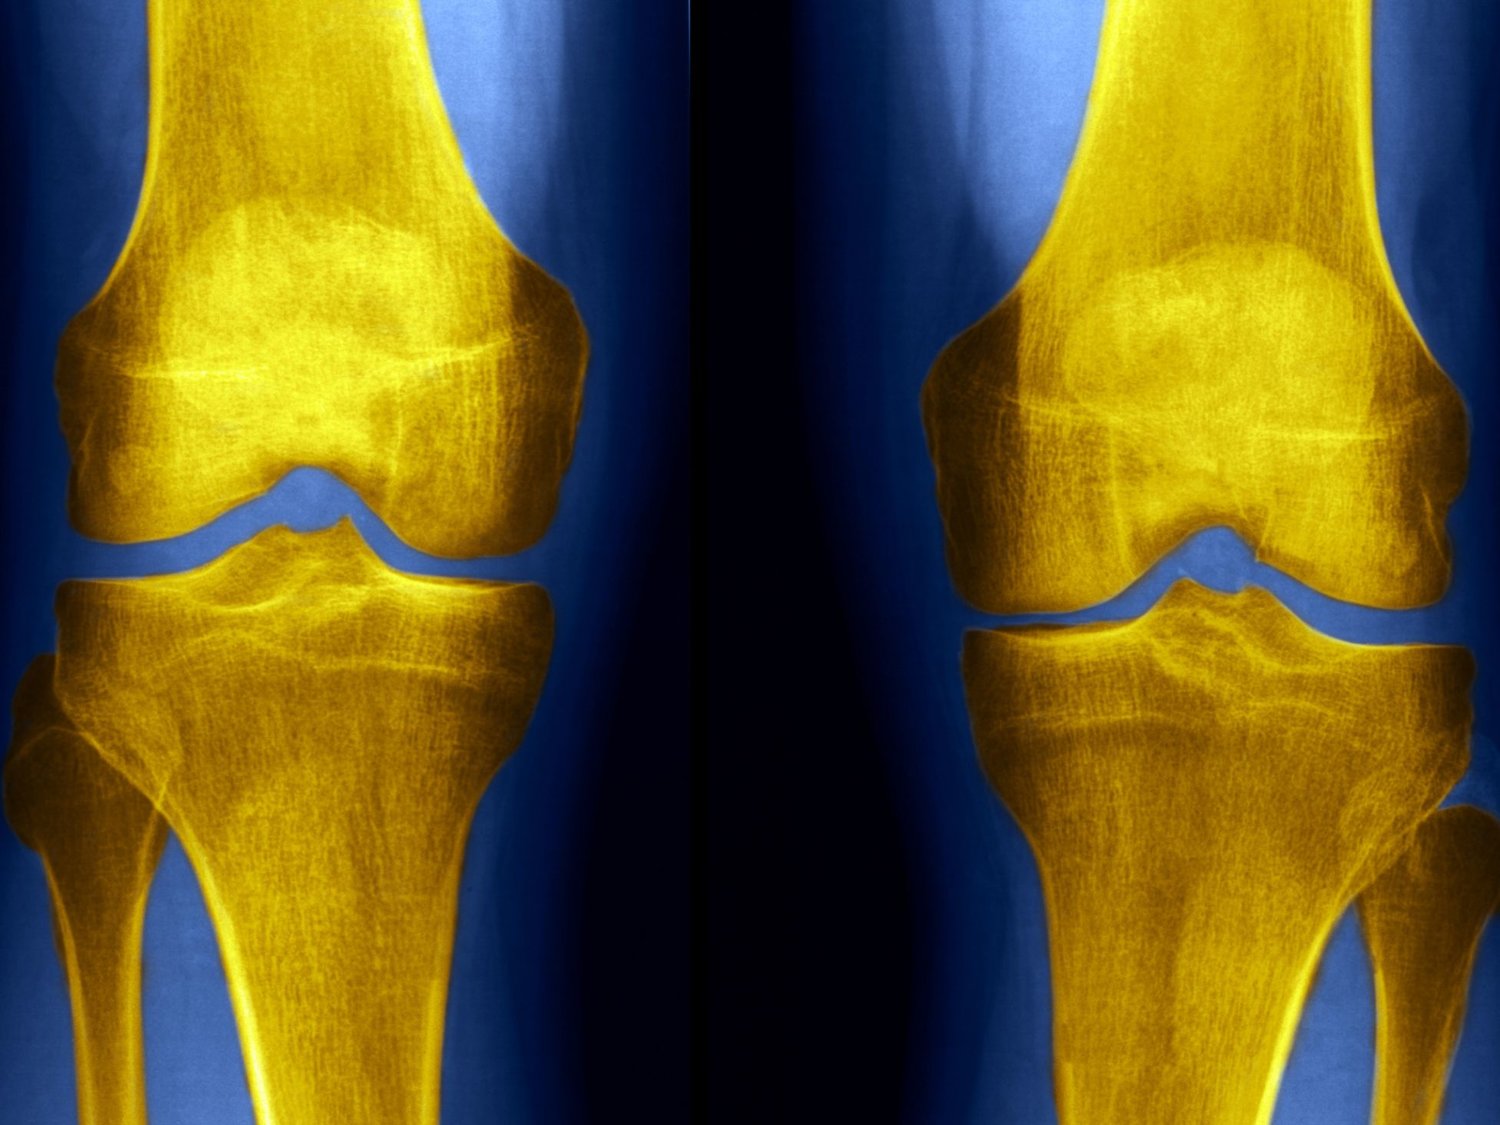

التهاب مفاصل الركبة واحد من أهم أمراض العظام التي يشعر بها فئة كبار السن تحديدا، وتتزايد فرص الإصابة مع زيادة الوزن، حيث يحمل مفصل الركبة عظمتي الفخذ والساق، ويتم تغطيتهما بمادة قوية ومرنة تسمى الغضروف، إلا أن تآكل هذا الغضروف تدريجيا يسبب التهاب مفاصل الركبة والتي يتم علاجها منذ السبعينات بـ حقن حمض الهيالورونيك، فماذا عن هذه الحقن؟ وهل فعالة في علاج التهاب المفاصل التنكسي؟

التهاب مفاصل الركبة

يحدث التهاب مفاصل الركبة عندما تتلف منطقة واسعة من عظام المفصل فيحدث الاحتكاك ضد بعضها البعض ويشعر المريض بالألم والالتهاب، مع العلم أن هناك عوامل خطورة تزيد فرص الإصابة بـ التهاب مفصل الركبتين.